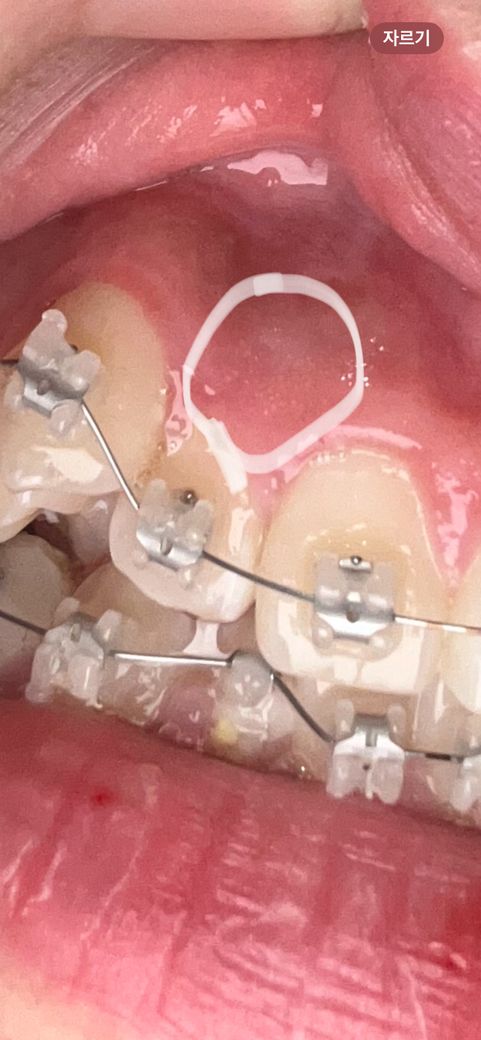

교정한지 일주일이 넘었는데 앞니가 밑에 있는이랑 닿을때마다 잇몸? 신경?이 찌릿찌릿하고 아파요 원래 이런건가요? 그리고 잇몸이 뭐라해야하지 사진처럼 막 하얀 점 같은것들이 생겻는데 저건 뭔가요?

• 2번 째 사진

잇몸에 생기는 것과 불편한 느낌은 일시적인 증상일 가능성이 큽니다. 교정 중에는 치아에 통증을 느끼기도 하고 다양한 잇몸 부작용이 나타납니다.